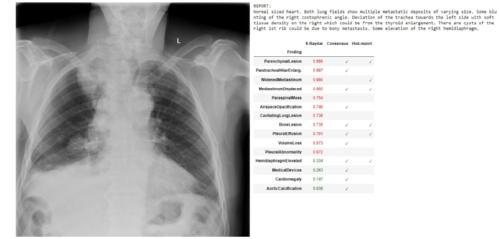

The AI software can scan X-rays as soon as they are taken for possible conditions and flags any abnormalities. It will then give a percentage chance of each of the abnormalities being present. The AI also understands the seriousness of the different conditions and will flag the more urgent ones to doctors accordingly.